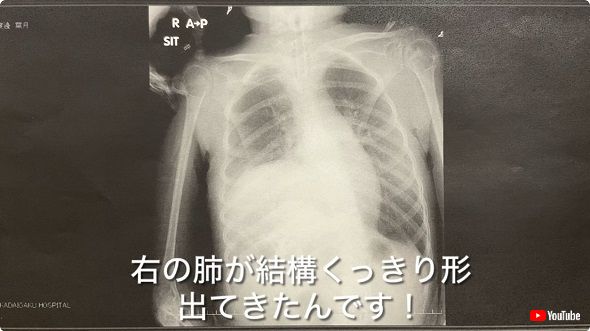

帰宅後の家族で今後の方針を語り合う中、お父さんが葉月ちゃんの肺の現状を知らせようと、先ほど撮影したレントゲン写真を公開。

しっかりと視認できる両肺の画像を前に、「右の肺が結構くっきり形出てきたんです」「たん出し頑張ったことによって無気肺(肺の一部もしくは全体に空気が入っていない状態)の部分が少しずつ良くなっているって」と声を上げ、葉月さんはもちろん家族で毎日酸素吸入など治療に励んだ成果が現れていることに大喜びの様子です。

お母さんが画像に映った右肺を指して、ぼやけることなくキレイなカーブの形状をしていると指摘するや、お父さんも「しばらく見てなかったね」「そういうふうにキレイなカーブは」と頷いていました。

なお、葉月さんは2023年10月に呼吸の苦しさから救急入院しましたが、その際に撮影されたレントゲン写真では、右肺は今回と異なって下の部分を中心に真っ白となっており、お父さんも「たんも取れるときはガッツリ取っていこう!」と大変そうな様子でベッドに横たわった娘に言い聞かせていました。